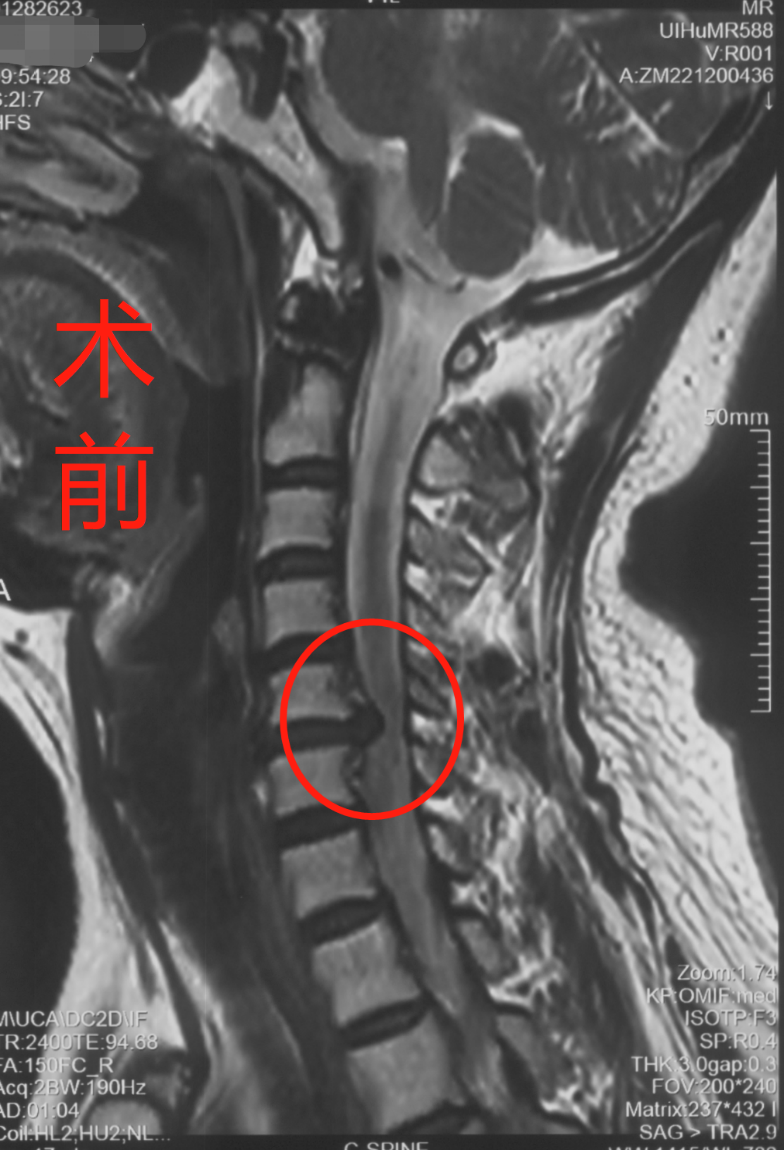

长航骨科:凶险的"脊髓型颈椎病"险些让他瘫痪!_手机搜狐网

周三待术?脊髓型颈椎病

脊髓型颈椎病